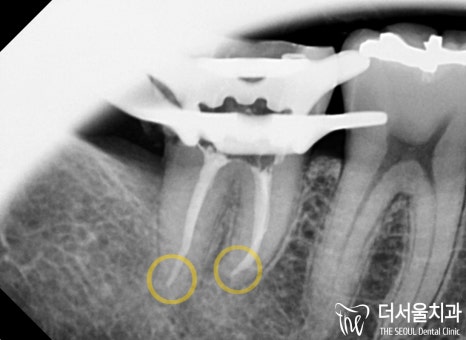

두 곳 모두 ‘근관치료’를 통해

문제를 개선하는 것으로 계획을 세웠습니다.

해당 술식은 병소가 심하게 퍼졌을 때

감염된 근관을 제거하고

치과용 수복재를 통해 채워 넣어주는 방법입니다.

여기서 주의해야 될 것은

두 곳 모두 어금니라는 점입니다.

존재하는 것들을 모두 찾아

세척, 소독, 충전을 거쳐야 되는데,

만약 여기서 미세한 곳이라도 놓쳐버리게 된다면

바로 시술 실패 및 재발, 부작용으로 이어지는 것이죠.

따라서 좀 더 주의 깊게! 신중하게!

진행해야 되는 곳들 중 하나입니다.